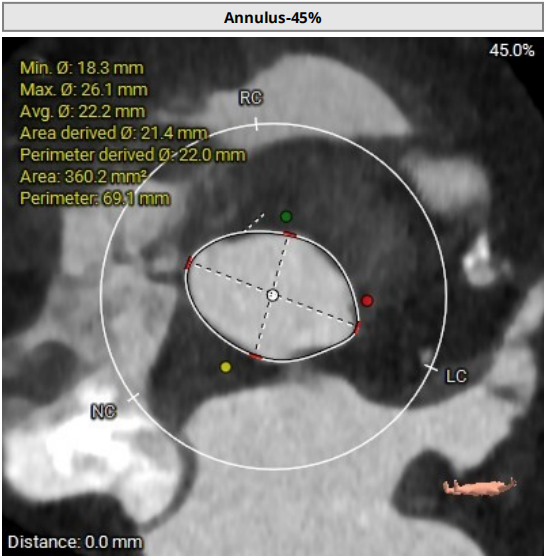

根部结构:Type1二叶瓣(L-R型),左右之间纤维钙化融合嵴,轻中度钙化伴瓣叶增厚,瓣环:22.0mm,左室流出道 :22.1mm,瓦氏窦:33.1mm,瓣上限制区(supra-8mm):21.5mm,极小心腔。

瓣环:22.0mm

LVOT:22.1mm

SOV:33.1mm(高:9.5mm)

瓣上限制区:21.5mm

STJ:30.9mm(高:23mm)

AAO:35.7mm